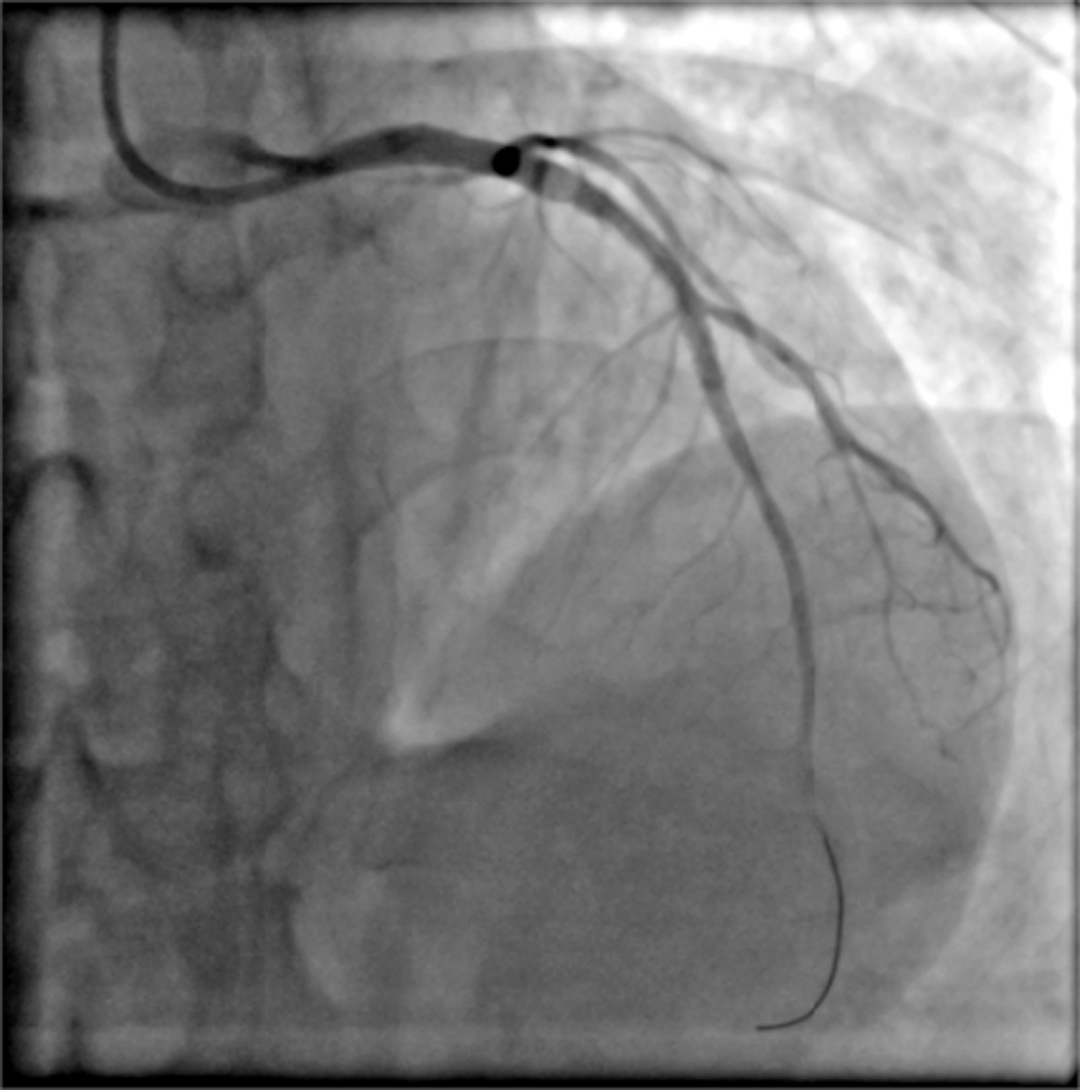

“准备除颤!继续心脏胸外按压!”心内科主任朱兴彪镇定地展开抢救,同时ICU行气管插管,维持患者生命体征。电除颤成功,但紧接着,室颤“电风暴”又来了,1次、2次、3次……大家都清醒的认识到,只有打通闭塞的血管,才能解决根本问题。在所有人的不懈努力下,前后历经25次电击除颤,最终开通闭塞血管并置入支架两枚,患者心率及血压逐渐恢复平稳,终于把患者从“鬼门关”拉了回来。

术后

术后,患者安稳转运至ICU,在医护人员的精心护理下,于09月20日康复出院。1月后,患者再次来我院心内科复诊,经复查支架情况良好,各项指标正常。